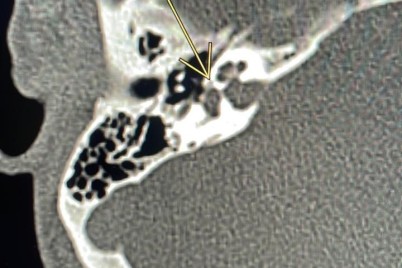

مكة المكرمة ـ إبراهيم البلوشي نجح فريق طبي بمركز الرأس والعنق وقاع الجمجمة بمدينة الملك عبدالله الطبية بالعاصمة المقدسة...

مكة المكرمة ـ إبراهيم البلوشي تمكن بفضل الله تعالى فريق طبي بمستشفى النور التخصصي عضو تجمع مكة المكرمة الصحي...